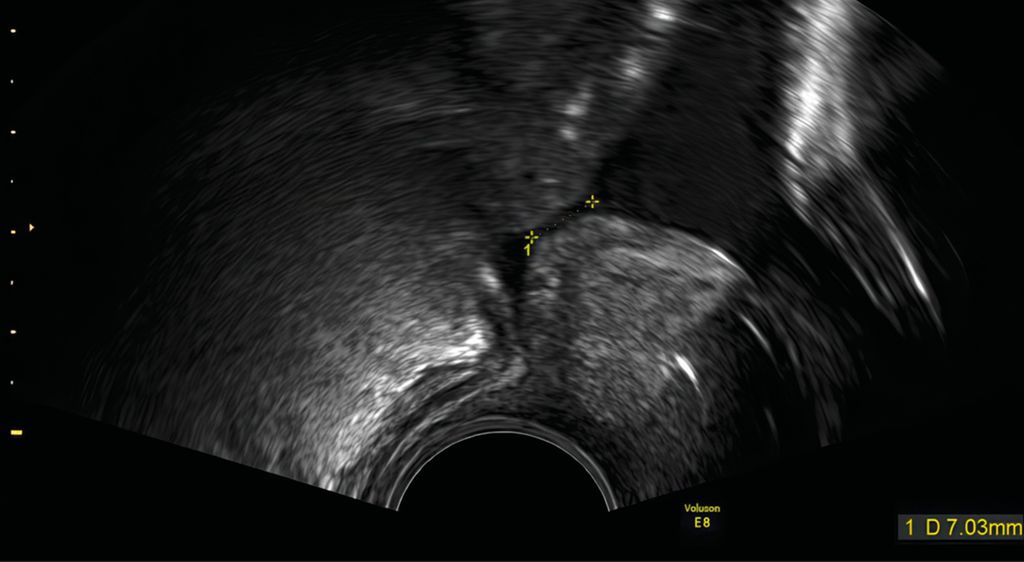

Zervixpessar

Eine Zervixinsuffizienz kann zu einem mechanischen Versagen des Gebärmutterhalses führen. Es gibt mehrere Hypothesen darüber, wie das Arabinpessar zur Vorbeugung von Frühgeburten beitragen könnte. Das Arabinpessar umschliesst den Gebärmutterhals, und verändert den Neigungswinkel des Zervikalkanals im Verhältnis zum Corpus uteri und reduziert den direkten Druck auf die Eihäute auf Höhe des inneren Muttermundes und auf den Muttermund (Abb. 2 und 3). Eine weitere Hypothese lautet, dass das Pessar den Zervixschleimpfropf schützt. Dies könnte dadurch erreicht werden, dass das Pessar die Anhaftung des verbleibenden Zervixgewebes unterstützt.19